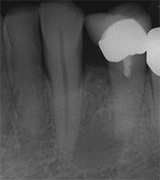

Aufbissempfindlichkeit an 33 veranlasste uns erstmalig in dieser Kieferregion zu röntgen. Mit grossen Augen sahen wir dann an, was uns auch ansah. Einen Knochendefekt dieser Grössenordnung mit seiner schaurigen Aura sieht man zum Glück nicht jeden Tag. Doch, obgleich das Alien dereinst Zahn 34 entsprang, war eine Behandlung nur am Zahn davor durchsetzbar. Dessen Wurzelfüllung erfolgte regulär nach 14 Tagen, neue Terminangebote aber wurden, weil angeblich nicht mehr nötig, verschmäht.

Keine 8 Wochen gingen noch in's Land, bis das mit Macht geschah, was lange schon erwartet war. Das Arbeitsprogramm bestand aus Eröffnung von Zahn 34 und einer Schwellung inkl. Drainage, am nächsten Tag dann noch Aufbereitung des Kanals mit Einlage. 2 Wochen später dann die Füllung plus einem als Resektion deklarierten Auslöffeln des Granu­lationsgewebes durch eine Mini-Öffnung, zu deren Verschluss eine Naht genügte.

3 Aufnahmen sind von 2001, die vierte vom Nov. 2006